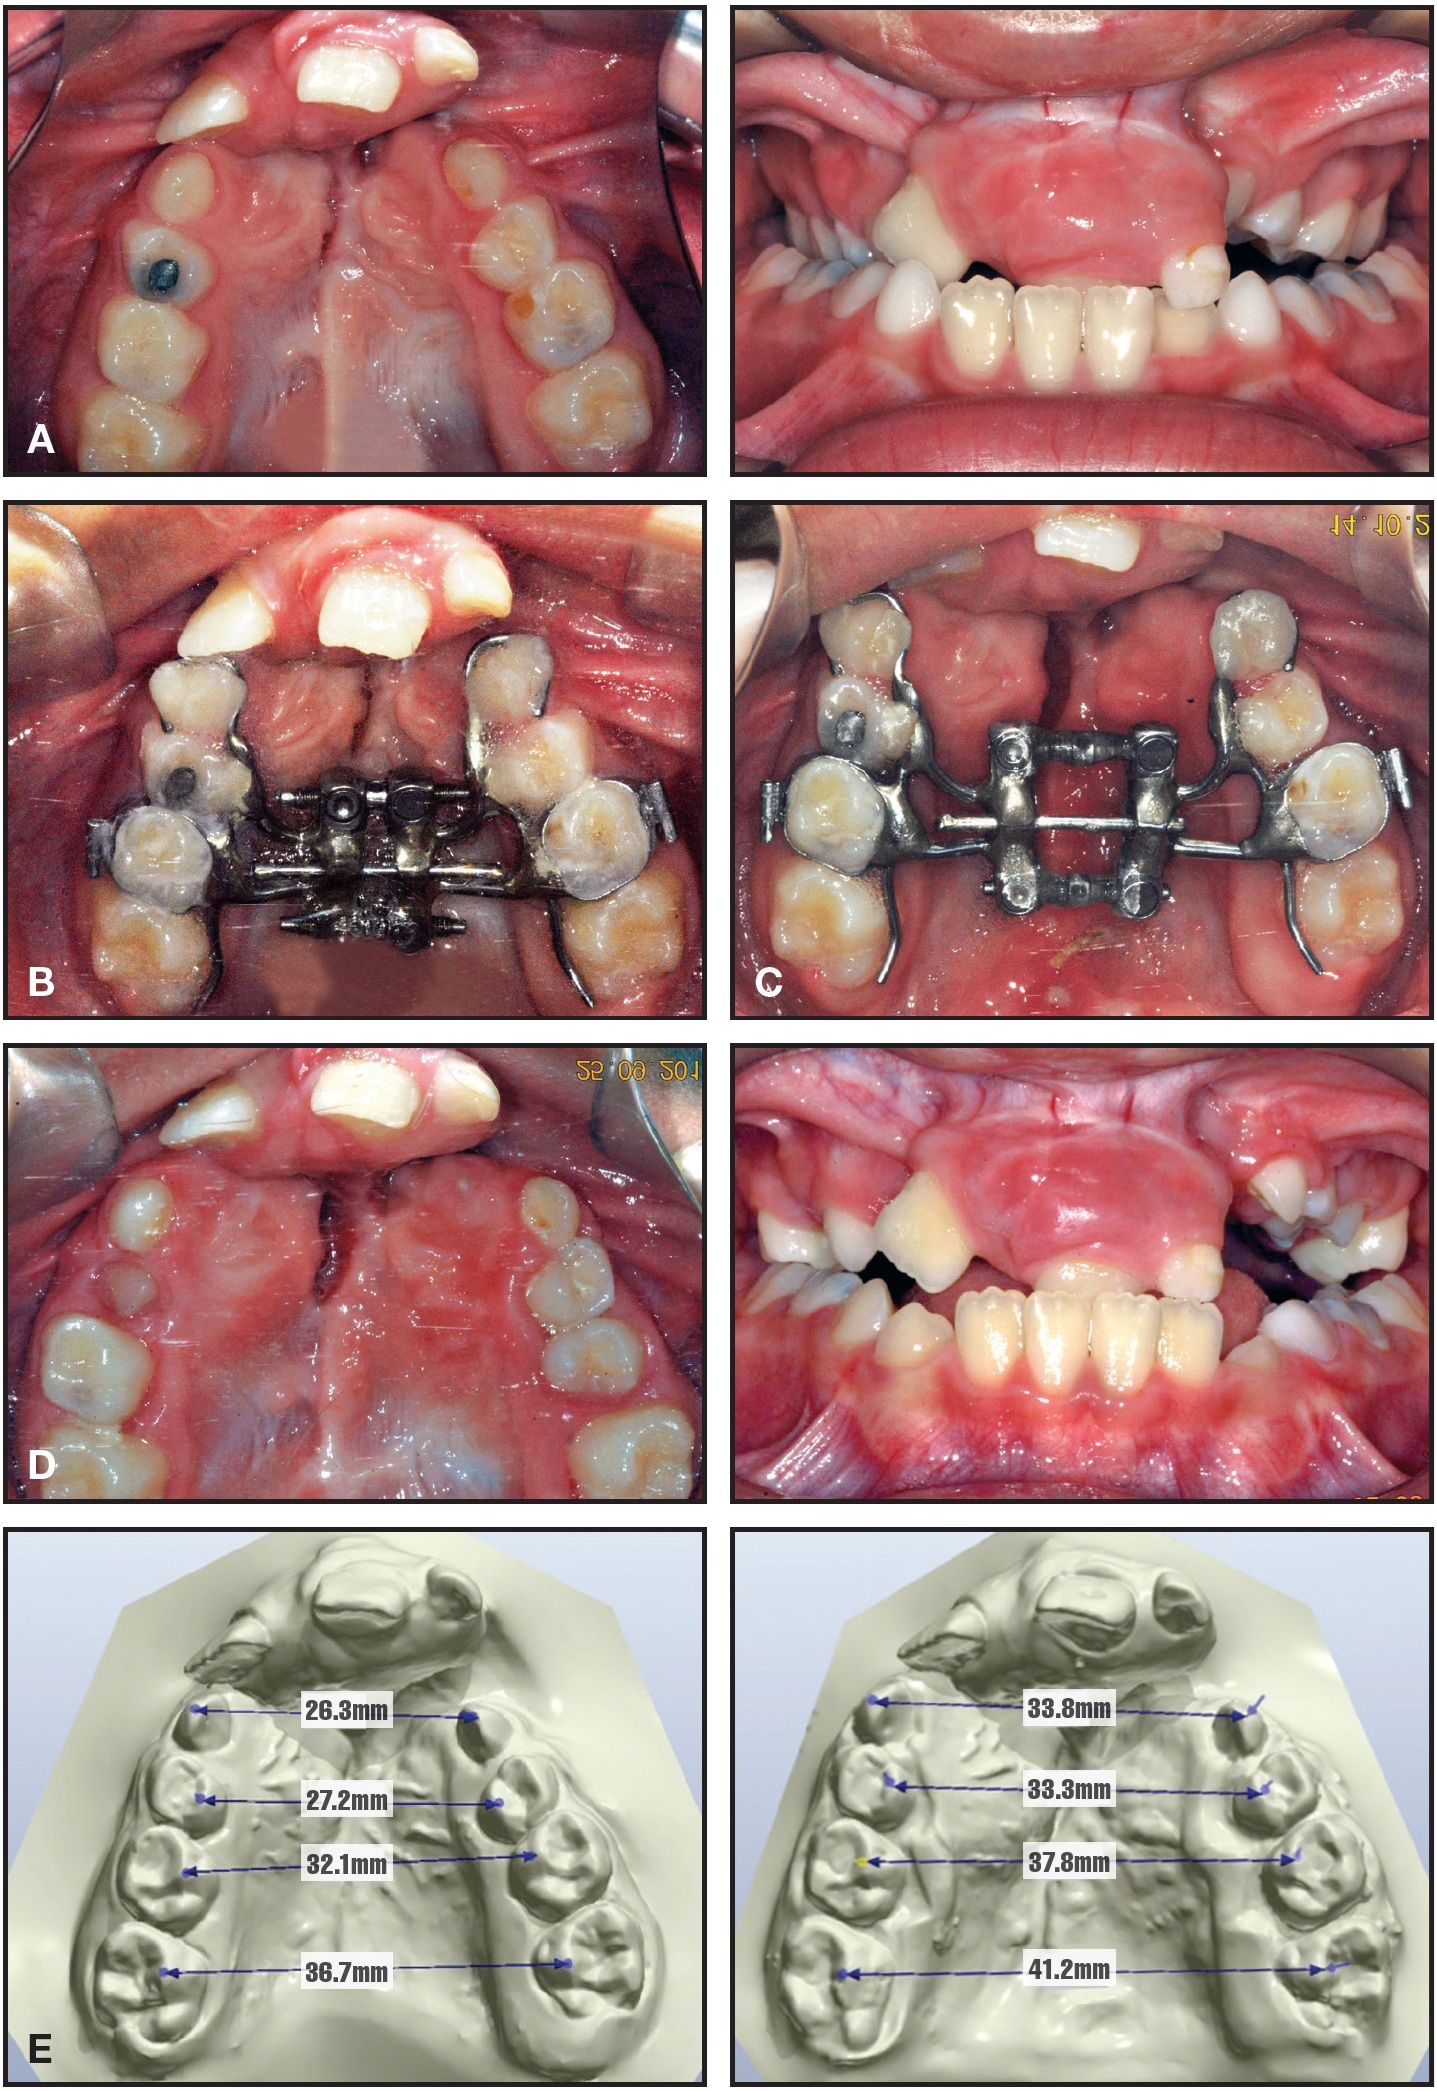

An 8-year-old male with bilateral CLP required even more differential expansion between the posterior and anterior segments (Fig. 4A). After an EDO was placed (Fig. 4B) and both screws were activated for five days, the anterior screw was activated for another four days (Fig. 4C). The canines were expanded 3mm more than the molars (Fig. 4D,E, Table 1).

Fig. 4 Case 2. A. 8-year-old male patient with complete bilateral cleft lip and palate. B. Placement of EDO. C. After five days of activation of both screws and additional four days of anterior-only activation. D. Six months later, after removal of expander. E. Comparison of palatal widths before and after expansion, showing 3mm differential between intercanine and intermolar expansion.